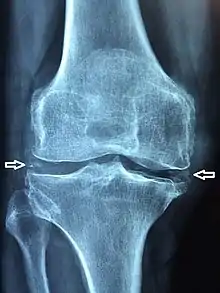

X-ray of a knee with chondrocalcinosis.

Medical imaging, consisting of x-ray, CT, MRI, or ultrasound may detect chondrocalcinosis within the affected joint, indicating a substantial amount of calcium crystal deposition within the cartilage or ligaments.[2] Ultrasound is a reliable method to diagnose CPPD.[8] Using ultrasound, chondrocalcinosis may be depicted as echogenic foci with no acoustic shadow within the hyaline cartilage[9] or fibrocartilage.[8] By x-ray, CPPD can appear similar to other diseases such as ankylosing spondylitis and gout.[2][4]